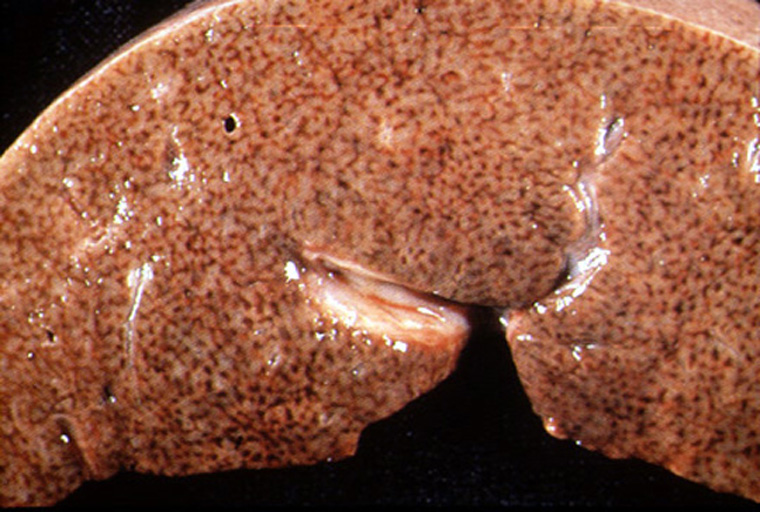

Liver-chronic passive congestion - CHF  Dr Ralph Leischner